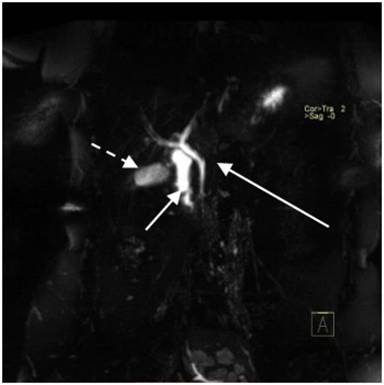

Pseudo-agenesis of the pancreas refers to the atrophy of the pancreatic body and tail secondary to acute/chronic pancreatitis with sparing of the head and uncinate process. MRCP/ERCP provide conclusive diagnosis in this condition by demonstrating minor ductal system in pseudoagenesis due to acquired pancreatic atrophy and its absence in dorsal pancreatic agenesis / pancreatic hypoplasia [2] (Figures 2, 3, and 4). Ultrasound is relatively insensitive in this regard and CT may not be sensitive always.

Figure 3. MRCP image showing common bile duct and ventral pancreatic duct (long arrow) draining head of the pancreas and non-visualization of dorsal pancreatic duct. Also seen are second part of the duodenum (short arrow) and gall bladder (dashed arrow). |